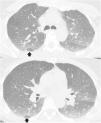

La TC torácica en espiración es una técnica complementaria de la inspiración que aporta valiosa información fisiológica y puede ser más sensible que las pruebas de función respiratoria para detectar atrapamiento aéreo. Tiene múltiples indicaciones, entre las más frecuentes están la enfermedad obstructiva de la vía aérea producida por bronquiolitis obliterante, asma, síndrome de Swyer-James, traqueomalacia, neumonitis por hipersensibilidad o sarcoidosis. En alguna de ellas, como la bronquiolitis obliterante, la TC espiratoria puede ser la única técnica de imagen que detecta alteraciones en las fases iniciales. Si queremos que sea de utilidad diagnóstica, hay que asegurarse de que el estudio tenga calidad suficiente. Para ello se recomienda explicar al paciente en qué consiste la prueba, emplear instrucciones precisas y realizar un breve entrenamiento antes de iniciar la adquisición. En este trabajo sugerimos estrategias para optimizar la técnica y proponemos un algoritmo para interpretar los hallazgos radiológicos en el contexto de la patología obstructiva pulmonar.

Expiratory CT scan is a complementary technique of inspiratory CT that provide valuable physiological information and may be more sensitive to detect air trapping than pulmonary function tests. It is useful in many obstructive airway diseases, including obliterative bronchiolitis, asthma, Swyer-James syndrome, tracheomalacia, hypersensitivity pneumonitis and sarcoidosis. In obliterative bronchiolitis, expiratory CT scan may be the only imaging technique that shows abnormalities in the early phase of disease. In order to obtain a good quality study, we should explain the procedure to the patient, use precise instructions and do some practice before image acquisition. Here we describe strategies to optimize the technique and propose an algorithm that help in interpretation of imaging findings in patients with obstructive airway disease.